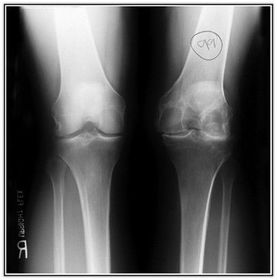

AP Bilateral Weight Bearing Knees 40 SID 14x17IR in wall BUCKY MANUAL TECHNIQUE for bilateral PHOTOTIME for unilateral - CR perpendicular to IR @ 1/2 in below apex of patella for average sized pts - CR angled 5-10 degrees cephalic for hypersthenic pts

How should the feet be positioned for the AP Bilateral Weight Bearing projection of the knees? rotated 5 degrees inward to get True AP